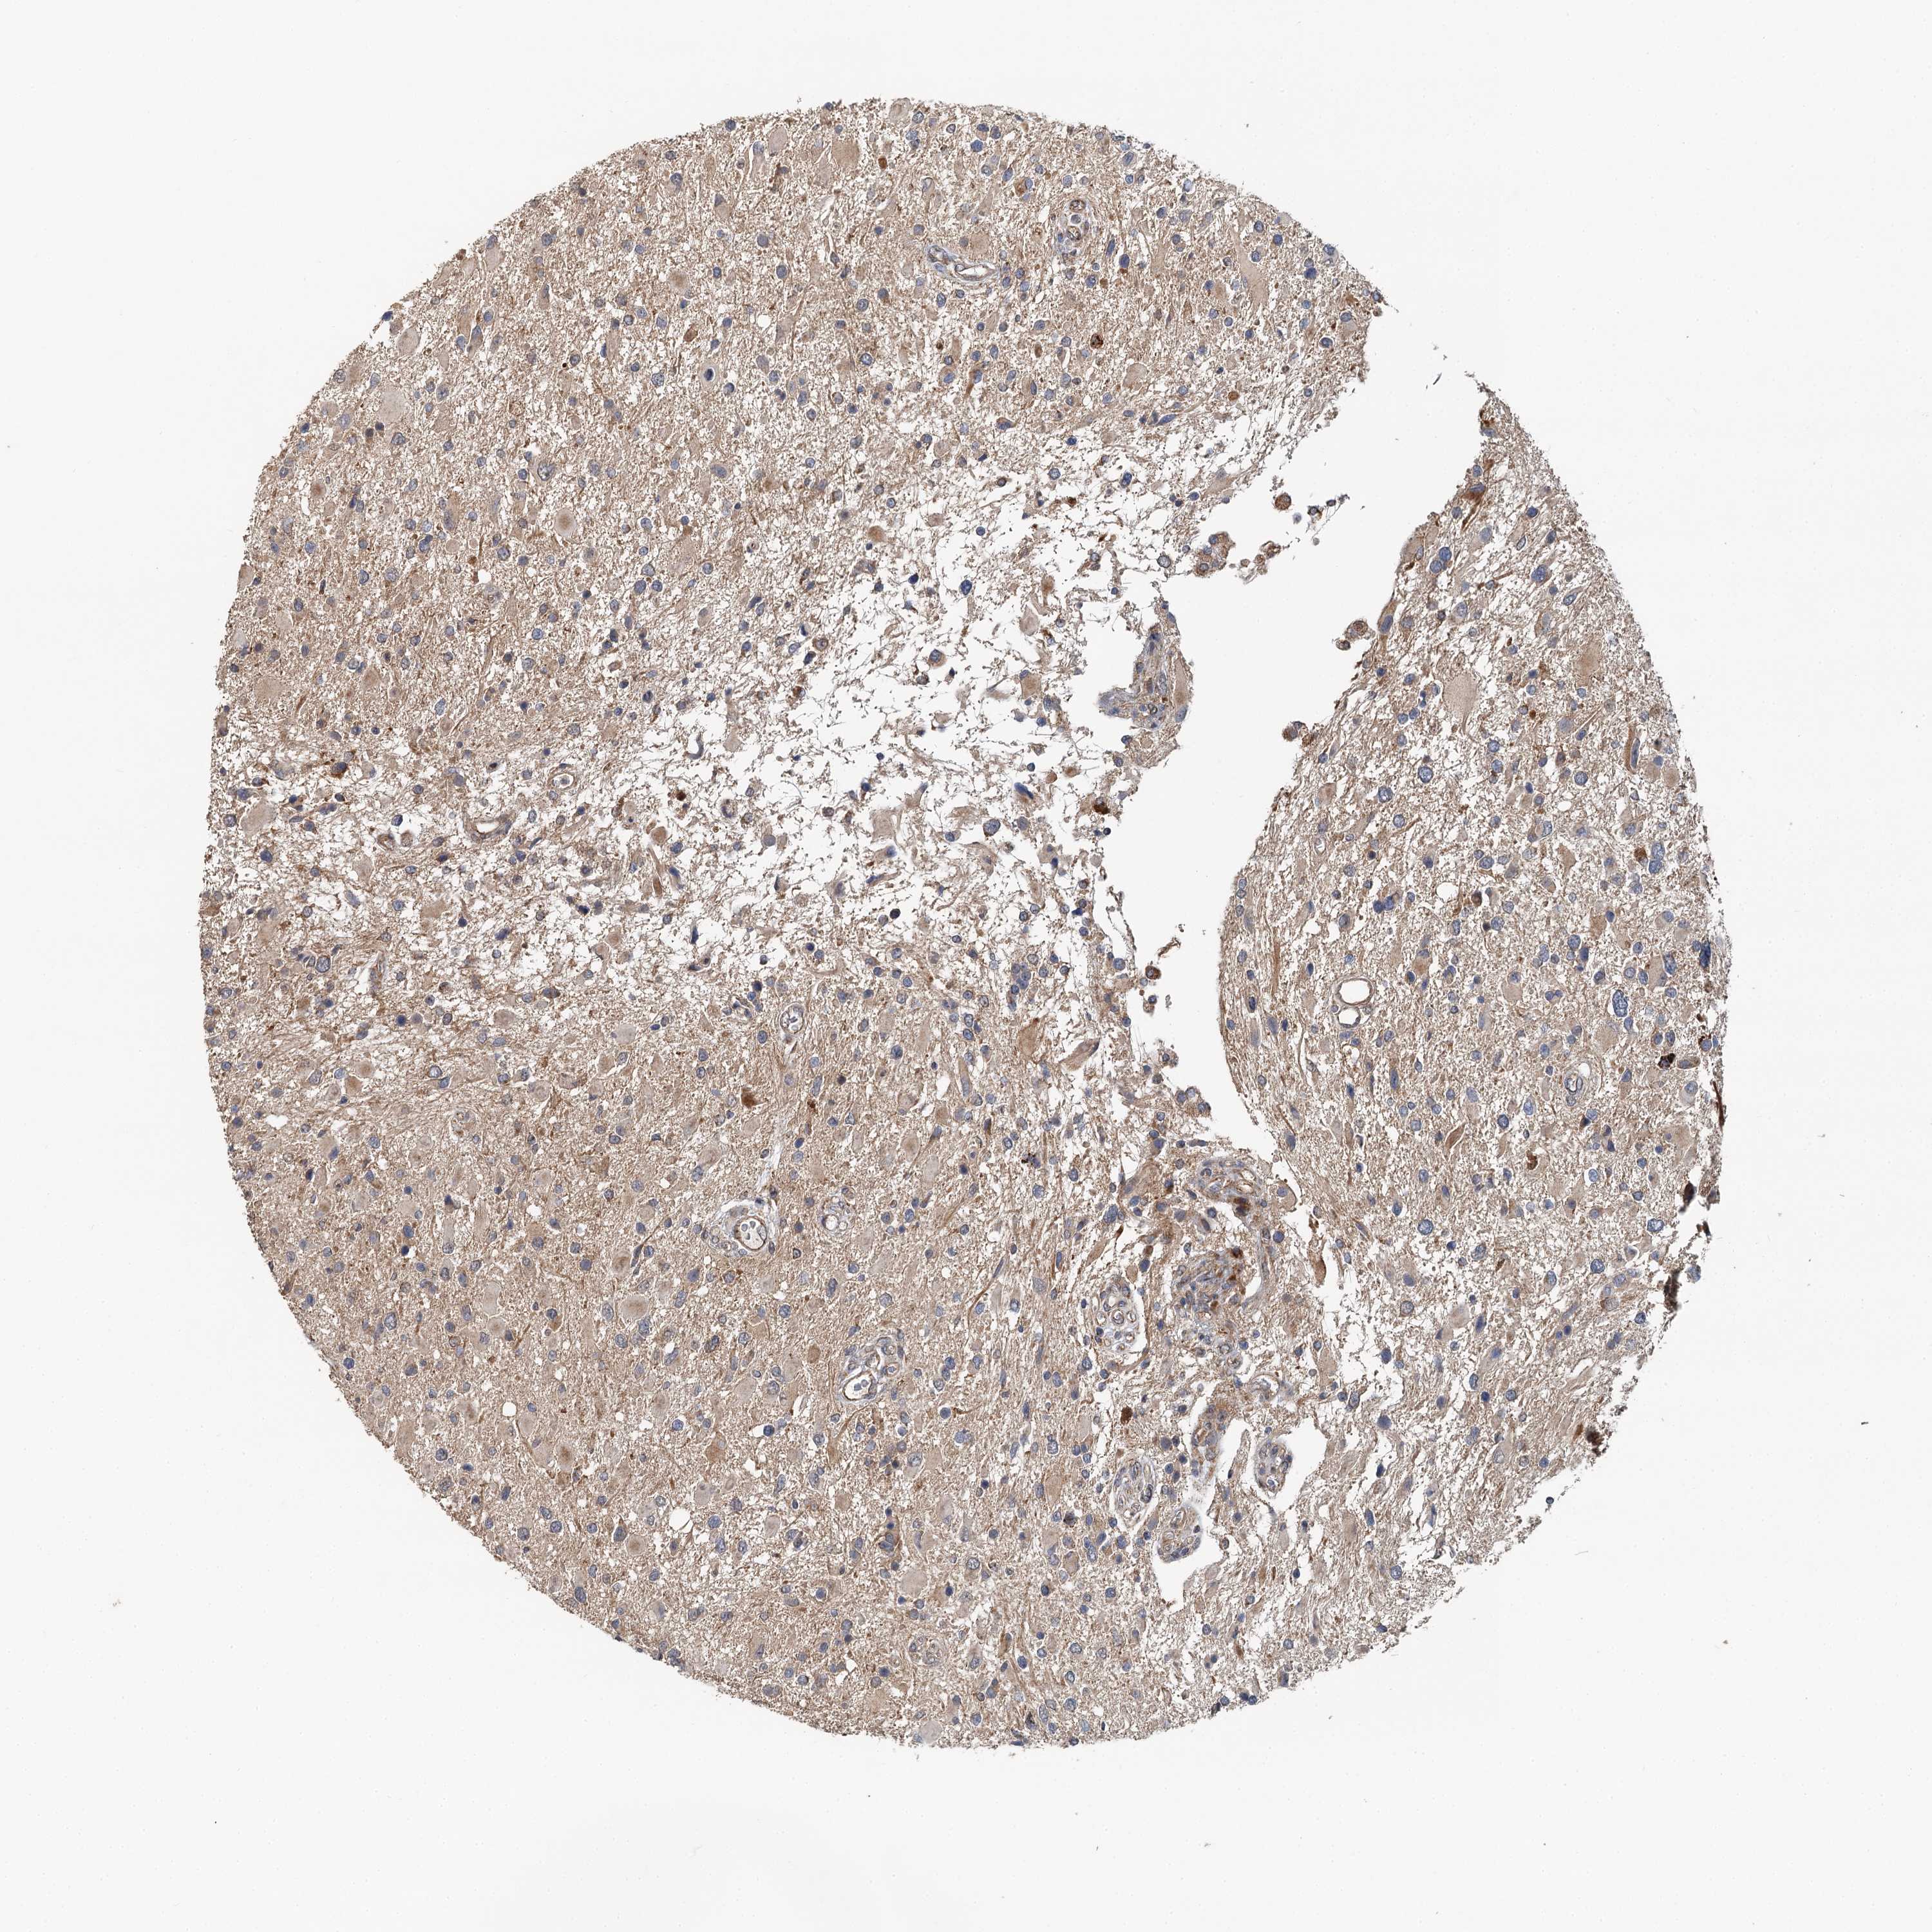

GLIOMA - Protein expressioni

A mouse-over function shows sample information and annotation data. Click on an image to view it in a full screen mode. Samples can be filtered based on level of antibody staining by selecting one or several of the following categories: high, medium, low and not detected. The assay and annotation is described here.

Note that samples used for immunohistochemistry by the Human Protein Atlas do not correspond to samples in the TCGA dataset.

Antibody stainingi

Antibody staining in the annotated cell types in the current human tissue is reported as not detected, low, medium, or high, based on conventional immunohistochemistry profiling in selected tissues. This score is based on the combination of the staining intensity and fraction of stained cells.

Each image is clickable and will lead to virtual microscopy that enables deeper exploration of all samples and also displays staining intensity scores, fraction scores and subcellular localization as well as patient and tissue information for each sample.

Antibody HPA014293

Antibody CAB037160

Staining

High

Medium

Low

Not detected

Intensity

Strong

Moderate

Weak

Negative

Quantity

>75%

75%-25%

<25%

None

Location

Nuclear

Cytoplasmic/membranous

Cytoplasmic/membranous,nuclear

Glioma, malignant, High grade

Glioma, malignant, Low grade